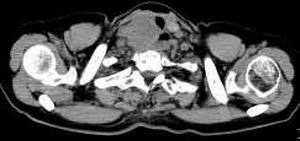

女,61岁,吞咽困难(包括开水)已久。

食道中上段癌并锁骨上窝淋巴结转移.

食道中上段中分化鳞癌伴锁骨上淋巴结转移